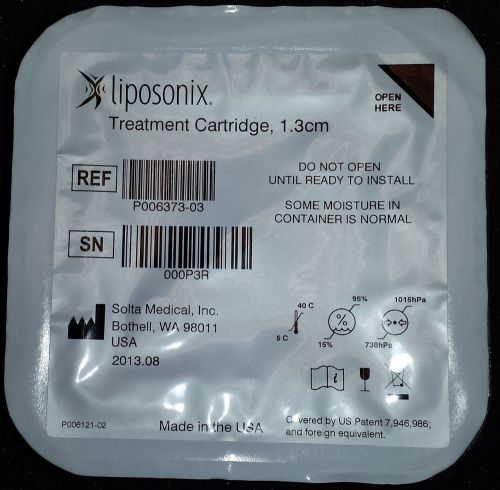

Liposonix Treatment Cartridge (Transducer Head)